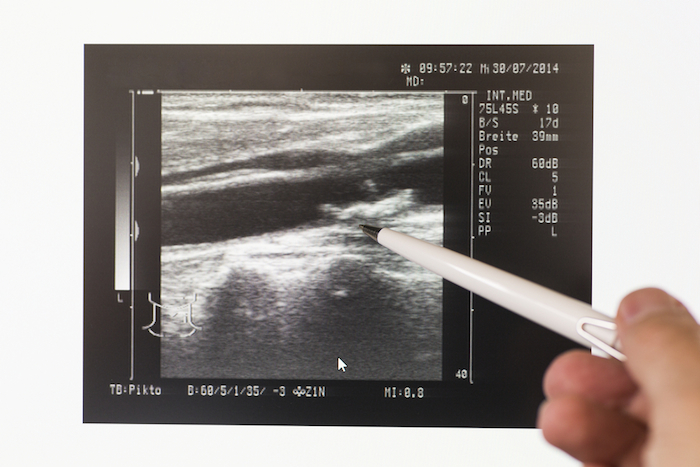

ULTRASONIDOS DE LA ARTERIA CARÓTIDA

¿Por qué normalmente no la necesitas?: Puede que hayas visto que ofrecieran esta prueba en una clínica móvil o una feria local de la salud. Esta prueba, que se promueve como una manera simple e indolora de evaluar tu riesgo de un ataque cerebral, busca obstrucciones en las arterias carótidas que se encuentran en ambos lados de tu cuello. Sin embargo, menos de dos por ciento de las personas que tienen bloqueos en estas arterias y que por lo demás no tienen otros síntomas terminan teniendo un ataque cerebral.

El examen no expone a las personas a la radiación, pero a menudo sugiere que hay un bloqueo cuando en realidad no lo hay, de acuerdo con un estudio realizado en 2014 por la revista Annals of Internal Medicine.

“Esto puede llevar a más pruebas e incluso a cirugías innecesarias para desbloquear las arterias, lo cual a su vez conlleva el riesgo de un ataque cerebral”, indica el doctor Michael LeFevre, M.D., vicepresidente de medicina familiar y comunitaria en la Escuela de Medicina de la Universidad de Missouri, y expresidente del Grupo de Trabajo de Servicios Preventivos de EU, el cual asesora al gobierno sobre asuntos de salud pública. De hecho, un tratamiento común para arterias carótidas obstruidas, llamado endarterectomía carótida, puede desencadenar ataques cerebrales en el dos al cuatro por ciento de las personas.

Es por eso que el equipo de trabajo, junto con la Asociación Estadounidense del Corazón (AHA), y el Colegio Estadounidense de Cardiología, no recomiendan pruebas de detección de ecografías para la mayoría de las personas.

Cuándo vale la pena realizarla: Los beneficios de la prueba superan los riesgos si tienes antecedentes de ataque cerebral o mini ataque cerebral (ataque isquémico transitorio), que a menudo está marcado por síntomas como adormecimiento o debilidad de un lado de la cara o dificultad para hablar o para entender.